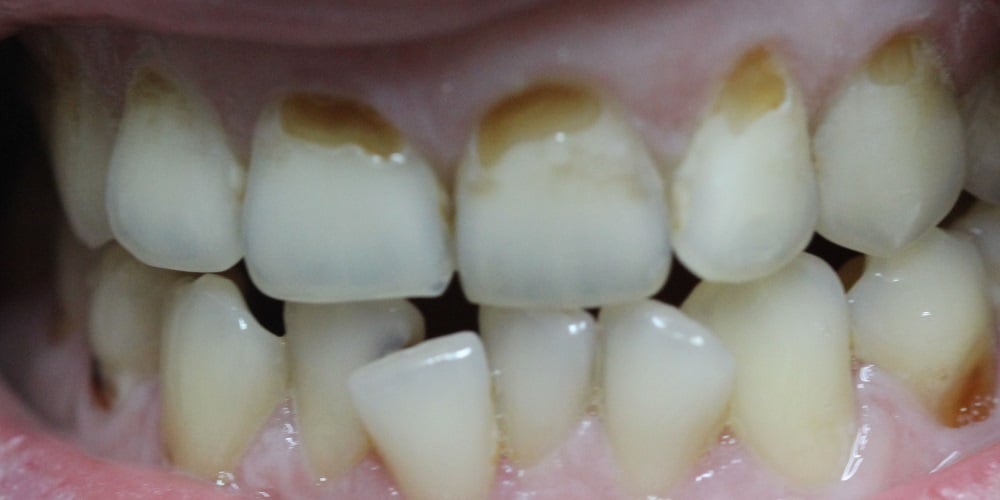

Эрозия зубов — это прогрессирующее необратимое истирание зубной эмали или дентина в результате химического растворения кислотами. Помимо эстетического дефекта и проблем со здоровьем полости рта, эрозия может привести к повышенной чувствительности и возможной потере пораженных зубов.

• Изменение цвета зубов. Зубы могут казаться более желтыми из-за обнажения дентина

• Прозрачность. Края передних зубов могут стать прозрачными.

• Трещины и вмятины. Если зубная эмаль начинает разрушаться, на зубах могут появиться трещины и небольшие вмятины вдоль жевательной поверхности. Когда эмаль разрушается, значительно увеличивается риск развития кариеса.